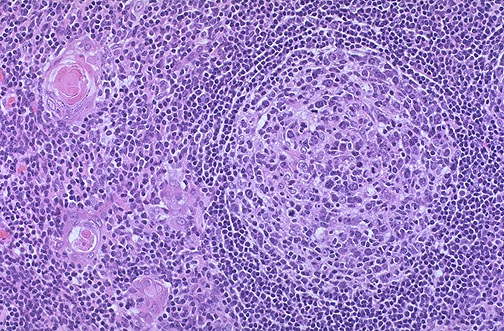

| The follicular hyperplasia of the thymus seen here in this case of thymic hyperplasia with myasthenia gravis is associated with autoantibody production. It is the acetylcholine receptor antibodies that diminish receptors in the motor end plates leading to the muscular weakness. |